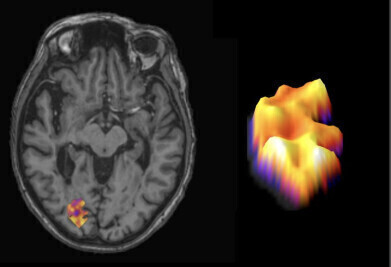

The image shows an MS lesion in the brain, marked in colour. On the right is a close-up image of this broad-rim lesion. Credit: University of Turku -

The study [1], led by Professor Laura Airas in collaboration with German and Dutch partners, found that the thickness of the inflammatory cell rim surrounding brain lesions strongly correlates with the severity and pace of MS progression. Their findings were published in Nature Medicine.

Using PET imaging data from 114 Finnish MS patients alongside detailed post-mortem brain tissue analysis from Dutch patients, the team discovered that wider inflammatory rims around lesions are linked to more aggressive disease advancement.

Professor Airas explained: “When microglial cells create a thick rim around MS lesions, their damaging activity extends deeper into healthy brain tissue, causing irreversible harm.”